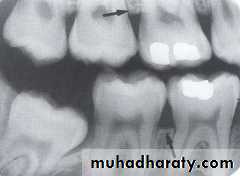

ENAMEL: Enamel is the most radiopaque of any tissue seen radiographically and cover the coronal portion of the tooth.

DENTIN: Dentin is found beneath the enamel layer of a tooth and surrounds the pulp cavity, the dentin appears radiopaque, but lighter than enamel.

PULP CAVITY: The pulp cavity consist of a pulp chamber and pulp canals, its contain blood vessels, nerve and lymphatic and appears relatively radiolucent on dental radiograph.